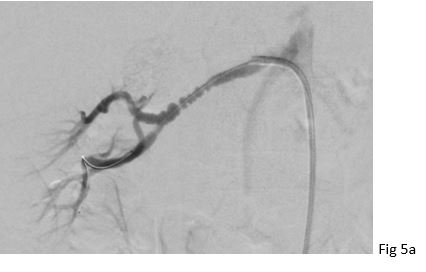

Figure 5: 37 year old female with fibromuscular dysplasia of the right renal artery. Digital subtraction angiography (DSA) showing the classical "string of beads" appearance of the right renal artery with stenosis in the mid segment in (a). DSA after ballon angioplasty without relevant stenosis in (b).